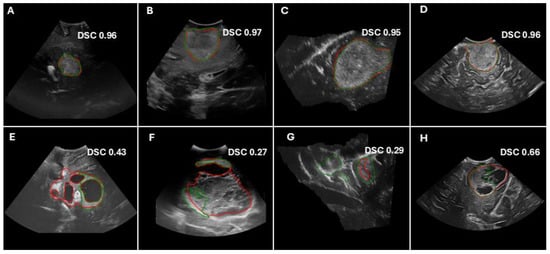

Figure 4.

Examples of model predictions and Dice similarity score (DSC) values for the hold-out test cohorts (A,B,E,F), as well as the external validation cohorts (C,G) (RESECT-SEG) and (D,H) (Imperial-NHS). The top panels show cases with good performance, whereas the bottom panels illustrate cases with poor performance. The ground truth tumor segmentations are delineated in red contours, whereas predicted segmentations are shown in green.